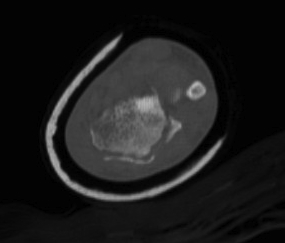

Dislocated Radiocarpal Joint CT 1Dislocated Radiocarpal Joint CT 2Dislocated Radiocarpal Joint CT 3